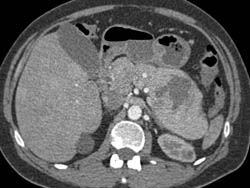

Diagnosis

Islet Cell Tumor